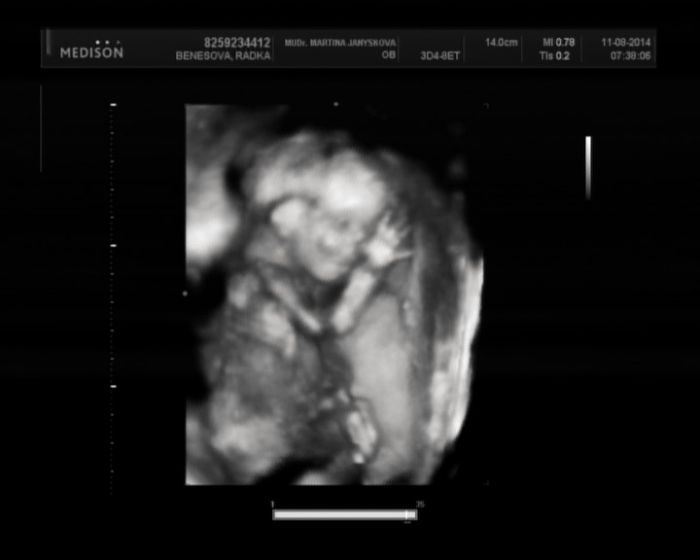

Radásku,gratuluji k podruhé potvrzené holčičce Kristýnce. Moc pěkná fotečka,jak si u tebe spokojeně hoví